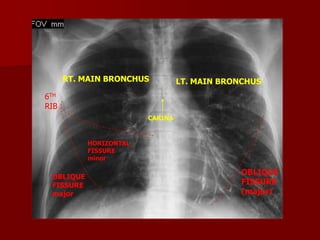

Pulmonary Fissures

Pulmonary fissures are formed with visceral

pulmonary pleura.

RIGHT LUNG

MAJOR FISSURE

OBLIQUE FISSURE

MINOR FISSURE

HORIZONTAL FISSURE

LEFT LUNG

Oblique fissure more clearly seen on Lateral view from

T4-T5 vertebrae to reach the diaphragm and 5 cm

behind the costophrenic angle on left And just behind

the angle on right.

Horizontal fissure more clearly Seen on P.A view

extending from Right hilum to 6th rib in the axillary line

RT. MAIN BRONCHUS

LT. MAIN BRONCHUS

6TH

RIB

CARINA

HORIZONTAL

FISSURE

minor

OBLIQUE

major

(major)